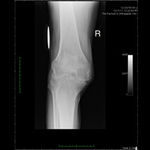

Patient seen with Bilateral Knee Pain and had been unable to walk for two (2) years.

On clinical and radiological examination, he was assessed as having Severe Primary Osteoarthritis of both knees.

Bilateral Total Knee Replacement was recommended, and performed on July 27th 2011. Since surgery, the patient has made good progress and can now mobilize with the aid of a walker.

His x-rays and clinical examination suggest good early outcome with a fully mobilized patient with pain free knees and the ability to walk independently.